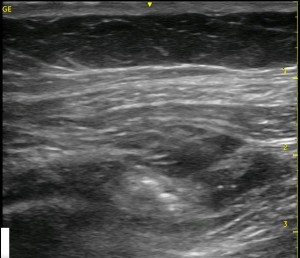

Sometimes, you can’t get the needle right where you want it, or a few confirmatory injections of local anesthetic distorts the local ‘architecture’ of the tissue. If you have done lots of TAP blocks, this has happened to you without question! You start with an awesome image, and end up with something like the image below.

Look at the images below. They appear to be a series of pictures arranged from the beginning of an injection to the end. In fact, no further injection is added. The first image is taken at the periphery of a TAP block, and the subsequent images are taken as the probe is slid closer to the center of the injection. They confirm that the needle is adequately placed within the appropriate plane though the central position is a bit difficult to interpret.